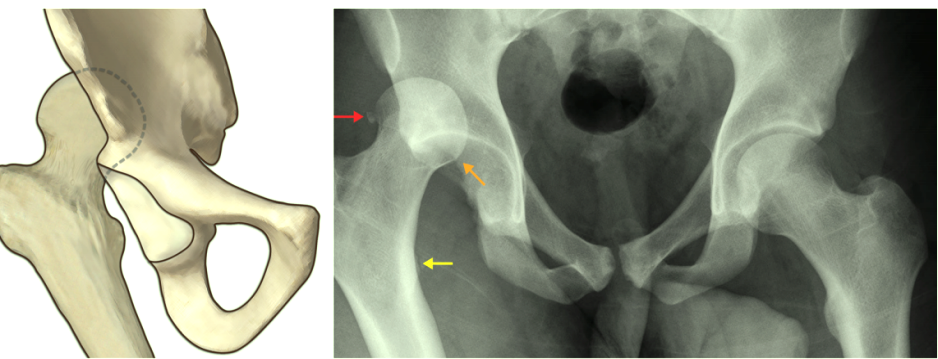

后脱位影像学:

股骨头较健侧缩小,股骨头与髋臼顶重叠;由于下肢内旋,小转子消失。

![]()

股骨头(橙色箭头)通常位于髋臼的上外侧,髋关节处于屈曲、内旋和内收状态。股骨内旋导致小转子明显性下降(黄色箭头)。注意本病例中有微小的髋臼后壁骨折(红色箭头)。